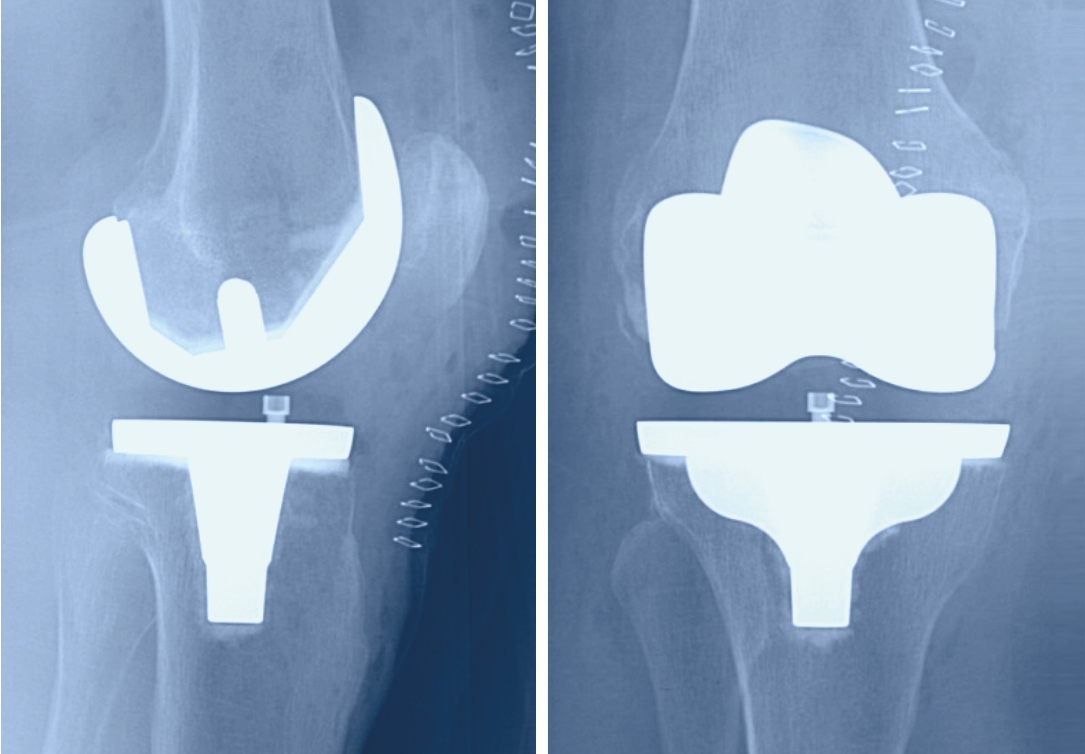

Bei der Operation werden die beschädigten Gelenkanteile oberflächlich abgetragen und ein künstliches Gelenk eingesetzt. Eine solche Prothese besteht aus drei Elementen: einem aus einer Metalllegierung bestehenden Ersatz für den Anteil des Oberschenkelknochens am Gelenk, einem für den Anteil des Unterschenkels und einem Kunststoffeinsatz.

Dieser wird zwischen die Metallteile gesetzt, um die ideale Führung des Gelenks zu gewährleisten und zu verhindern, dass die Metalloberflächen sich aneinander reiben. Je nach Ausweitung der Arthrose besteht heute die Möglichkeit, nicht immer das ganze Knie zu ersetzten sondern gezielt Teilprothesen zu verwenden. Dies hat den Vorteil, dass nur der beschädigte Gelenkanteil ersetzt werden muss.

Die beschädigten Oberflächen des Gelenks werden unter Zuhilfenahme von Schnittschablonen abgetragen, damit das Ersatzgelenk passgenau eingebracht werden kann. Zur genauen Platzierung der Schnittschablonen werden konventionelle Metallinstrumente verwendet, es können aber auch personifizierte Instrumente oder eine Computernavigation zum Einsatz kommen. Durch die Schnittsetzung und die Implantation der Prothese werden grosse Abweichungen der Beinachsen korrigiert, leichte O- oder X-Beine, die der Patient allenfalls schon immer hatte, werden aber belassen.

Der Zugang erfolgt über einen Hautschnitt vorn über der Kniescheibe. Damit eine gute Sicht aufs Gelenk möglich wird, wird es auf einer Seite der Kniescheibe eröffnet. Zur Fixierung der Prothesenteile am Knochen wird meist Knochenzement verwendet.